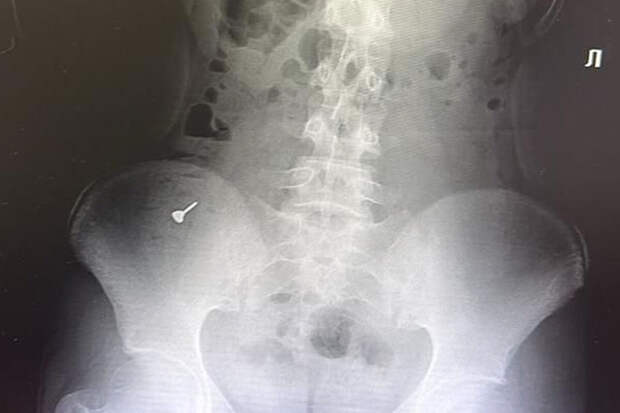

Школьница обратилась с жалобами на боли в животе. Врачи выяснили, что подросток раскрутила украшение для пирсинга и случайно проглотила трехсантиметровую часть от него.

Обследование показало, что деталь осела в области слепой кишки."Благодаря своевременному обращению инородное тело удалось удалить эндоскопическим способом – выполнить колоноскопию и удалить часть пирсинга из просвета слепой кишки", - рассказал хирург больницы Владимир Хабалов.